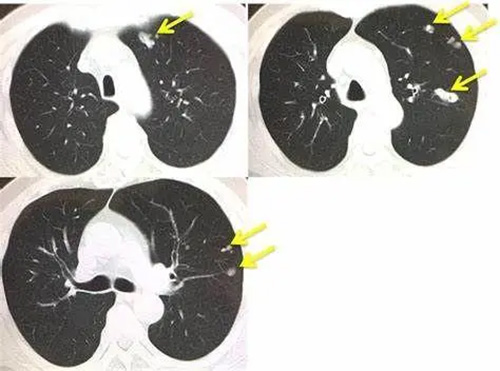

Lung cancer is the most rapidly increasing malignant tumor with the fastest increasing morbidity and mortality, which has been troubling medical workers. Clinical studies have found that about 15% of non-small cell lung cancer (NSCLC) cells are driven by EGFR gene mutations. These EGFR-dependent cancer cells can be treated with EGFR inhibitors.

However, there are still some cancer cells that depend on the AXL gene for survival. These tumors have a greater ability to advance and can transition between sensitive and resistant states. After the end of treatment, the residual AXL-dependent tumor can recur and metastasize. This is also one of the important reasons why lung cancer is difficult to treat.